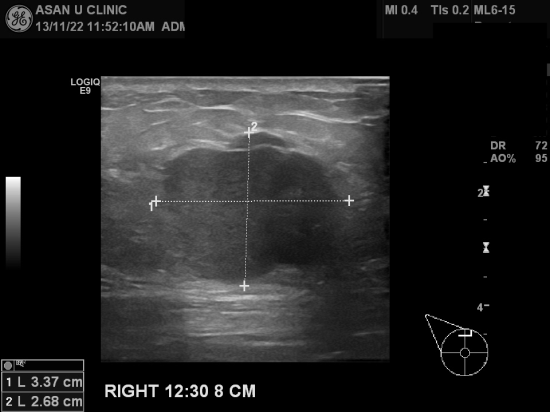

아산유외과 개원후 40번째 유방암진단.

우측유방에 만져지는 몽우리를 주소로 내원하시어

유방초음파와 중심핵생검으로 침윤성 유방암이 진단되셨습니다.

진단당시 암크기자체가 3cm가 넘는 혹이어서 마음이 아픕니다.

유방이 치밀유방이셔서 크기가 이정도가 되어서야 만져진 건지

본인유방의 자가검진을 안하셔서 그런지 구분할 수는 없지만

조금더 일찍 알았더라면하는 아쉬움이 남는 것은 사실입니다.

그러나 완치를 향해 달려가는데는 너무 늦은 것은 없으리라 생각됩니다.